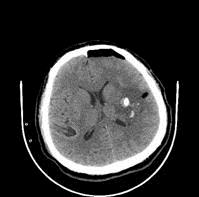

A.当出血超过一定量,需要手术治疗。

B.幕上20ml幕下10ml

C.当出血压迫明显造成神经功能损害,需要手术治疗。